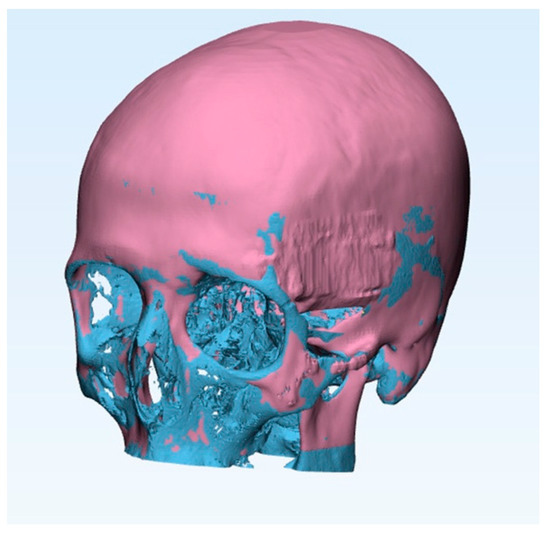

- Case #5: After 11 days post-surgery a CT was performed to check the complete removal of the tumor and that the SB was integrating without causing foreign body reaction or inflammation. After 2 years post-surgery, osteointegration was fully successful, with the reconstruction of the temporal and sphenoid bone. The bone was perfectly regenerated, and the patient’s cranial anatomy was completely reconstructed (Figure 5e). When we compared the two regions of interest in the post-surgery CT, we observed that the second one included a greater amount of bone. The bone was grown not only within the SB plaque but it was also remodeled to restore the correct skull anatomy; as a result, the right and left sides were symmetrical.